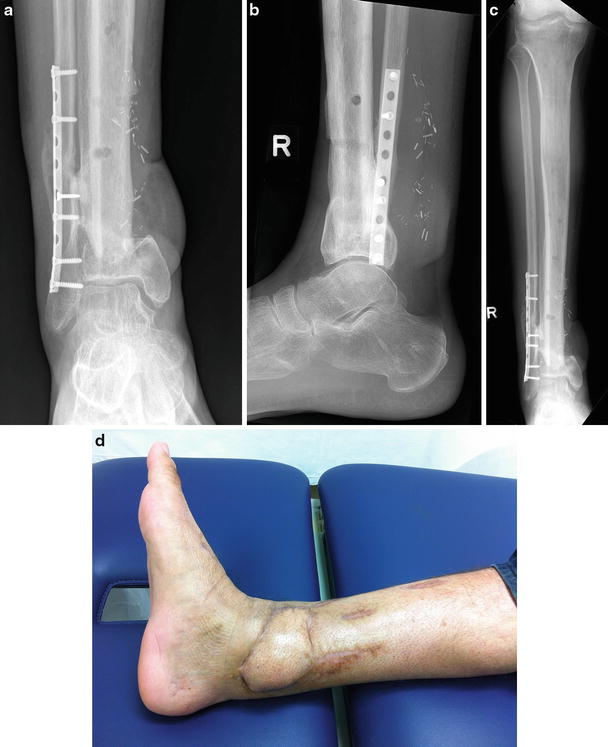

- The doctor may order basic x-rays. Depending on your unique health history and your treatment needs, the doctor may order additional laboratory tests or specialized x-rays.

- Basic elbow x-rays are taken from the front and side. Additional x-rays, taken at 2 different angles, also are routine.

Surgery

Sometimes an operation to repair your broken elbow is the best choice. This is particularly true if you have an open, or compound (a fracture in multiple pieces), elbow injury.

Elbow injuries that damage nerves and blood vessels often need to be fixed in the operating room. Medical researchers have found that certain types of broken elbows heal better if they are repaired in the operating room.

- Hardware problems: Doctors sometimes repair broken elbows with wires, pins, screws, plates, and other pieces of hardware.

During your elbow repair surgery, Dr. Dupay puts your bones back in place, sometimes securing them with metal pins or screws. This helps hold your bones together while they heal.